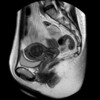

病院に着いた後、初めて会う医師から先日の骨盤MRIの結果を聞かされ。

2.5cmの粘膜下筋腫と、筋層内にも最大で1.5cmのものが数個だそうで。

子宮って赤ちゃんが育つ場所なので大きい臓器だと思われがちですが、通常時は内部の大きさは1×3cmくらいなんだそうですね。

そこに2.5cmの筋腫が張り出していたので、MRI画像では子宮の中はほとんど筋腫で埋まっていました。